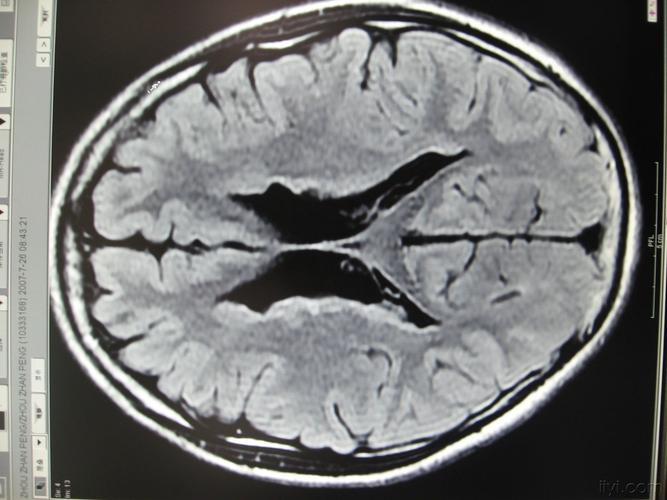

脑灰质异位,脑灰质异位图片

脑灰质异位_人体磁共振成像解

典型病例-脑灰质异位症

脑灰质异位症1例

脑灰质异位

医影学堂丨八个病例带你看懂脑灰质异位的三种类型